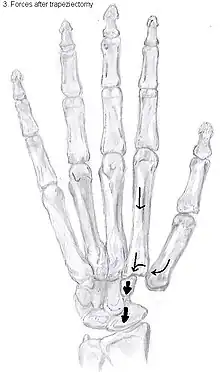

Trapeziectomy

During trapeziectomy,[30] the trapezium bone is removed without any further surgical adjustments. The trapezium bone is removed through an approximately three centimeter long incision along the lateral side of the thumb. To preserve surrounding structures, the trapezium bone is removed "by splitting" it into pieces.

An empty gap is left by the trapeziectomy and the wound is closed with sutures. Despite this gap, no significant changes in function of the thumb are reported.[27] After the surgery, the thumb will be immobilized with a cast.

Trapeziectomy with tendon interposition

Some physicians still believe that it is better to fill the gap left by the trapeziectomy. They assume that filling the gap with a part of a tendon is preferable in terms of function, stability and position of the thumb. This is based on the assumption that interposition can help maintain the space between the metacarpal and the scaphoid, which will improve comfort and capability. Neither of these assumptions is supported by experimental evidence.

During trapeziectomy with TI, a longitudinal strip of the palmaris longus tendon is collected. [31] If this tendon is absent (which is the case in 13% of the population), half of the flexor carpi radialis tendon (FCR) can be used.

The tendon is then formed into a circular shape and placed in the gap, where it is stabilized by sutures.[12]

Trapeziectomy with ligament reconstruction

Another technique is used to reconstruct the volar beak ligament after trapeziectomy. The rationale is that ligament reconstruction(LR) helps maintain the gap between the metacarpal and the scaphoid, and that a larger gap is associated with greater comfort and capability.[32] Again these possibilities are not supported by experimental evidence.

During this procedure the anterior oblique ligament is reconstructed using the FCR tendon. There is a wide variety in techniques to perform this LR, but they all have a similar goal.

Trapeziectomy with LRTI

Some physicians believe that combining LR with TI will help maintain gap between the metacarpal and the scaphoid.[33] And that doing so will improve comfort and capability. Keep in mind that these aspects of the rationale are not supported by experimental evidence. The evidence suggests that all of these procedures have comparable long-term results.